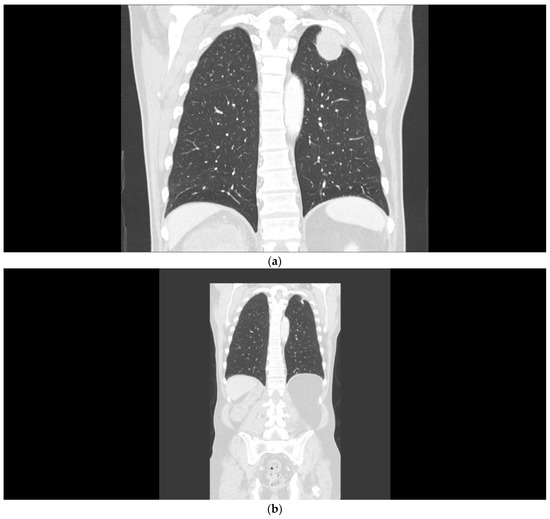

A 68-year-old man presented in March 2020 with a large tumor of the right kidney with synchronous metastases to the lungs, mediastinum, left adrenal gland, and extensive retroperitoneal lymphadenopathy (Figure 1a). The medical history was otherwise unremarkable. The patient underwent cytoreductive nephrectomy regardless of the presence of poor prognostic features according to the IMDC, including anemia, hypercalcemia, thrombocytosis, interval to therapy initiation, and Karnofsky performance status (KPS) 2, in April 2020. Histological examination confirmed a renal cell carcinoma with sarcomatoid and rhabdoid features. In May 2020, the patient received four cycles of nivolumab (3 mg/kg) plus ipilimumab (1 mg/kg) given every three weeks. Within a few weeks of therapy, the patient reported significant relief. Lab tests, including blood count and serum calcium, normalized, and KPS improved to 0. A follow-up CT scan showed partial response in all evaluated lesions (Figure 1b). The only adverse event was itching, that did not require any intervention. The patient continued with nivolumab monotherapy at a 480 mg flat dose until April 2021, when the therapy was interrupted due to Common Terminology Criteria for Adverse Events (CTCAE) grade 3 dermatitis. Systemic prednisone was initiated at 0.5 mg/kg, and the rash decreased within a few weeks. Upon improvement, the therapy with nivolumab was reintroduced. After 25 months, in June 2022, the patient remains on therapy, with a minimal residual tumor on CT scan and no additional adverse events.

Figure 1.

(a) Patient 1, pretreatment CT of the chest demonstrating lung metastases. (b) Patient 1, marked tumor reduction after the combination regimen of ipilimumab with nivolumab.